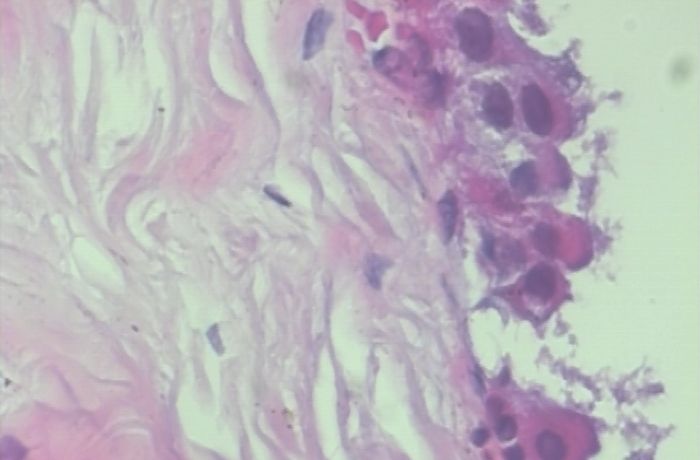

以上两张图片是恶性样本